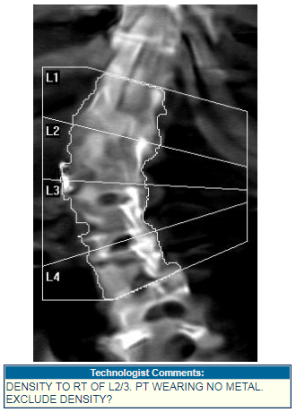

- BoneStation allows technologists to pass information to reading physicians via “scan comments”, which are entered on the DXA and appear in BoneStation.

- When a reanalysis is required, BoneStation facilitates communications between the reading physician and technologist. The reason for reanalysis is described to the technologist. The scan is also tracked as awaiting reanalysis – so staff will not lose track of it.